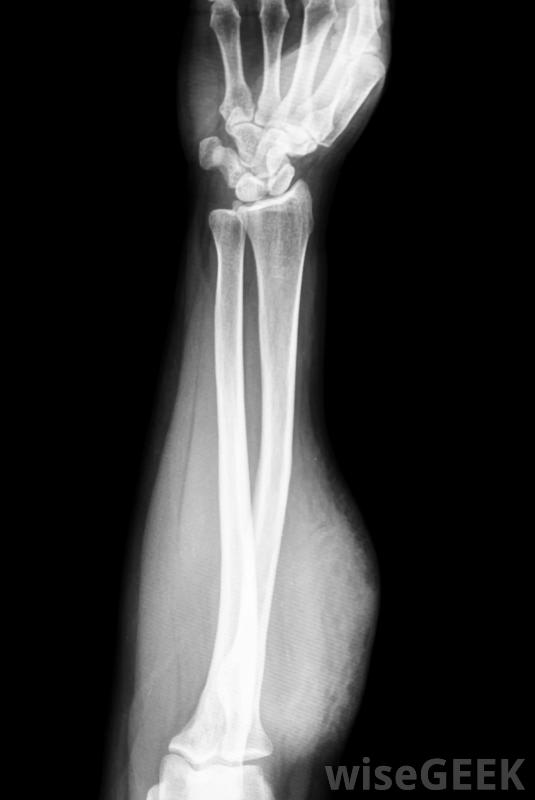

骨化性肌炎是骨骼開始在肌肉內生長的一種不尋常的情況,有時也被稱為異位骨化。這種情況可以通過x射線圖像來識別,這些圖像將顯示肌肉內和不應該出現骨骼的位置的骨沉積。治療方法取決于骨生長的位置、潛在原因和患者的...

骨化性肌炎是骨骼開始在肌肉內生長的一種不尋常的情況,有時也被稱為異位骨化。這種情況可以通過x射線圖像來識別,這些圖像將顯示肌肉內和不應該出現骨骼的位置的骨沉積。治療方法取決于骨生長的位置、潛在原因和患者的年齡等因素。骨化性肌炎可在X光片上顯示有幾個原因可以導致骨化性肌炎。在某些人中,它是遺傳性的。人們會在他們的肌肉中進行性骨生長,并且隨著時間的推移,這種情況在一些病人中可能會致命,在一種被稱為進行性骨化纖維發育不良(FOP)的罕見遺傳病中,對病人組織的損害會導致骨的生長,隨著時間的推移,會導致全身廣泛的異位骨化在受傷后對一個區域進行結冰以防止炎癥可能有助于降低骨化性肌炎的風險,人們沒有已知的遺傳條件,會導致骨化性肌炎,這種情況出現的結果是創傷有脊髓損傷和癱瘓的人都有危險,深部肌肉損傷導致內部血腫,如足球等運動中的踢傷。在這種情況下,隨著肌肉的愈合,大腿或手臂肌肉內的骨骼會生長由于運動損傷而經歷過深部肌肉損傷的人可能容易患骨化性肌炎。可以采取一些措施為了降低受傷后骨化性肌炎的風險。有些藥物可以用于脊椎損傷患者,對于損傷護理的常規建議,如預防炎癥的糖霜,似乎也有幫助。在治療損傷時,與有經驗的醫生合作也是很重要的,這樣可以及早發現并發癥的跡象當在一個不應該發生骨生長的地方發現骨生長時,醫生首先要確定病因。如果某人有遺傳疾病,原因可能已經很明顯了,但是如果某人沒有或沒有相關疾病的家族史,可以進行一些檢查,同時進行廣泛的患者訪談,進一步了解病人和情況。一旦確定病因,就可以討論治療方案。有時,多余的骨頭會自動被身體吸收,尤其是外傷性骨化性肌炎,如運動損傷引起的骨化性肌炎在其他情況下,可能會嚴重到需要手術切除骨頭。一般情況下,建議采取觀望的方法,定期檢查病情是否進展或保持穩定。那些脊髓損傷和癱瘓的人患骨化性肌炎的風險增加。